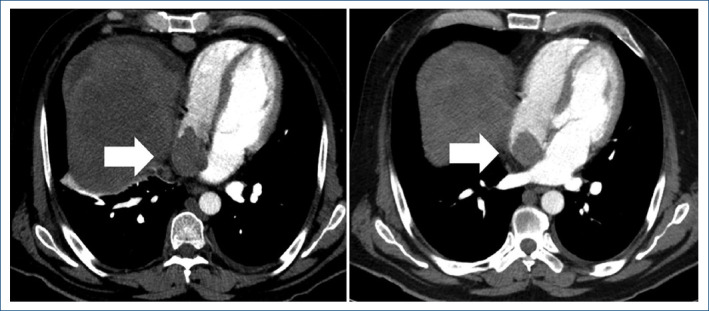

Hepatocellular carcinoma with inferior vena cava tumor thrombus extending into cardiac chambers: case report.